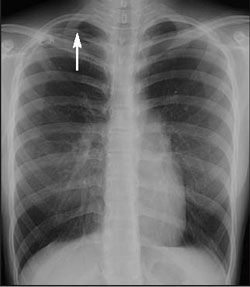

The chest radiograph shows a moderate pneumothorax on the right (Figure 1).

The presence of pneumothorax is usually confirmed by plain chest radiographs. A visceral pleural line without vessel markings is a key diagnostic finding.3 Radiographs may also show hyperlucency of vascular and lung markings. Chest CT can help distinguish preexisting lung conditions, such as neoplastic disease, from spontaneous pneumothorax when the diagnosis is uncertain.2,4

In this patient, a pigtail catheter was used to aspirate air from the pleural cavity; serial chest radiographs performed over the following days showed gradual lung re expansion (Figure 2). She was discharged after 7 days and was scheduled for follow-up with her primary care physician.